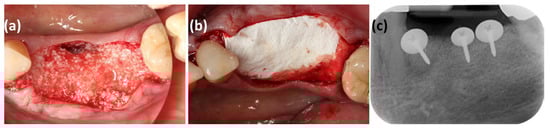

Implant Treatment Combining Interpositional and Strip Gingival Grafts in Post-Traumatic Sites of the Aesthetic Region: A 6-Year Case Report and Mini-Review

In implant treatment in the aesthetic zone, high aesthetic quality is required in addition to functionality and long-term stability when reconstructing defects in peri-implant tissues. Post-traumatic cases often present with extensive loss of both hard and soft tissues, making the selection of an appropriate grafting method essential. This report describes a case in which an interpositional gingival graft (IGG) and a strip gingival graft (SGG) were combined to regenerate peri-implant soft tissue following guided bone regeneration (GBR), maintaining favorable tissue morphology and aesthetics for six years. The patient was a 53-year-old woman who suffered trauma after falling down stairs, resulting in a fractured bridge in the right maxillary canine region and crown fracture. The traumatized tooth was extracted, and GBR was performed to restore hard tissue volume. Subsequently, IGG and SGG were used to improve soft tissue thickness, interproximal papilla height, and a healthy mucogingival junction (MGJ). A cantilever implant prosthesis was selected as the final restoration. Over six years, no gingival recession or marginal bone loss was observed, and excellent aesthetic stability was maintained. A mini-review of published reports on IGG and SGG demonstrated their efficacy in enhancing soft tissue volume. The findings of this case suggest that a comprehensive approach—including bone augmentation, soft tissue grafting, and prosthetic design—can provide predictable, long-term aesthetic and functional outcomes in complex post-traumatic cases (223). Full article

Figure 1